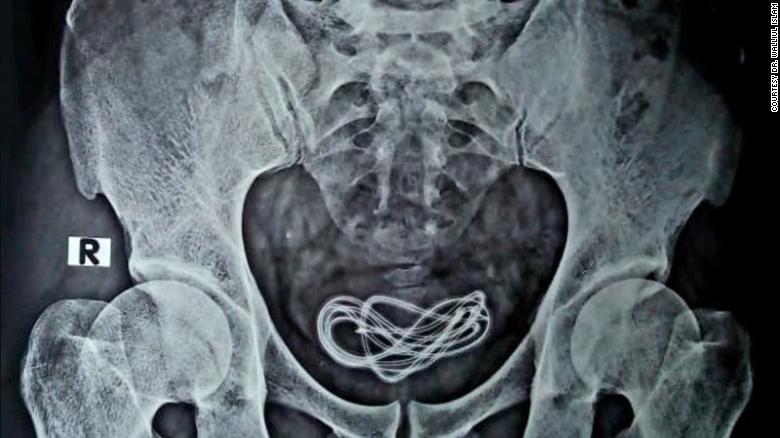

Surprised, Islam conducted an X-ray while the patient was on the operation table. It revealed that the cable was in fact in the man’s urinary bladder. The cable was removed and the patient is recovering well.

Doctors in India have removed a 2-foot long mobile phone charger from the bladder of a man who had inserted the cable into his penis.